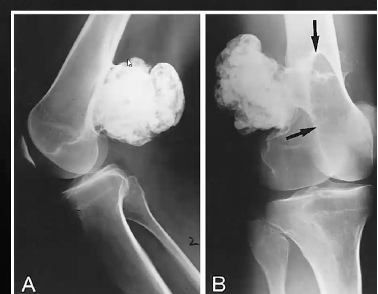

Tumeur à cell géante (ostéoclastome) : 80% bénin 20% Malin

- 20-40 ans

- Prompt à fx patho

- Touche les os longs, subarticulaire, près plateau physe, soap bubble apparence

- « Soap bubble appearance », plusieurs compartiments

- Bien défini, petite zone de transition (bénin)

- Moins bien défini et longue zone de transition (malin)

- Distal radius ++ (malin)

- Risque de tourner en ostéosarcome